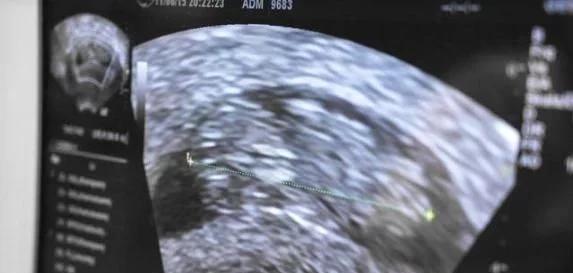

孕期到底要不要做B超检查?B超作为现代医学产检的主要手段之一,它可以检测到胎儿的基本发育以及羊水等情况,除了传统B超外,现在又衍生出了三维、四维彩超,可以全方位、更清晰的观察胎儿状况,帮助胎儿健康出生,做到优生优育。

B超检查是孕期的一种常见检查手段,医学上全程是B型超声检查,B超是一种非损伤性和无痛苦的检查方法。超声波是一种机械波,产生的只是热能,而且进行超声检查的时间一般都不会超过10分钟,声能控制都在安全范围内。对于准妈妈来说,只要是正常的B超检查次数,对胎宝宝是没有影响的。